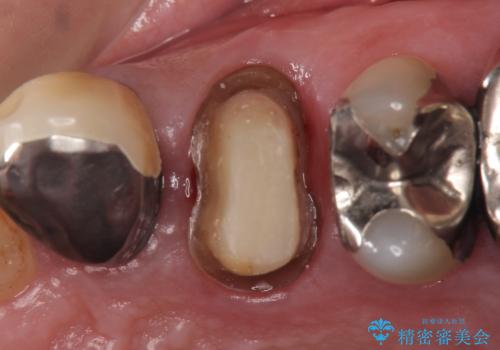

PGA(ゴールド)クラウン 脱離した銀歯の治療

- 古い銀歯が外れたので診て欲しいといらっしゃった方の症例です。

再根管治療後、PGA(ゴールド)クラウンによる補綴を行いました。

- PGA(ゴールド)クラウン…¥80,000、仮歯…¥10,000、ファイバーコア…¥20,000費用は治療当時の料金となります